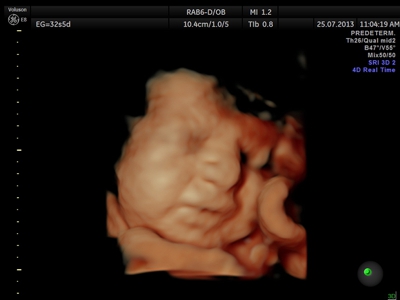

Si bien la Ecografía 4D HD/5D puede realizarse en cualquier etapa del embarazo, recomendamos realizarla entre las semanas 24 a 32 de gestación ya que se pueden observar rasgos bien definidos en el bebe.

Fotografías de ecografías 4D HD/5D

Haga click sobre las imágenes para ampliar